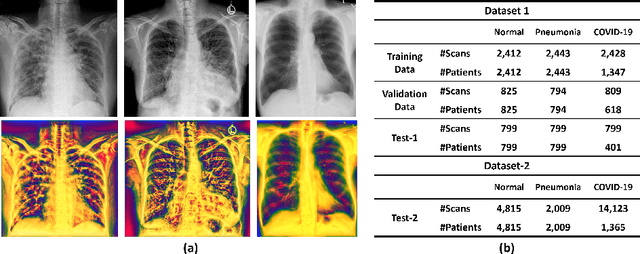

Abstract:Recently, the outbreak of the novel Coronavirus disease 2019 (COVID-19) pandemic has seriously endangered human health and life. Due to limited availability of test kits, the need for auxiliary diagnostic approach has increased. Recent research has shown radiography of COVID-19 patient, such as CT and X-ray, contains salient information about the COVID-19 virus and could be used as an alternative diagnosis method. Chest X-ray (CXR) due to its faster imaging time, wide availability, low cost and portability gains much attention and becomes very promising. Computational methods with high accuracy and robustness are required for rapid triaging of patients and aiding radiologist in the interpretation of the collected data. In this study, we design a novel multi-feature convolutional neural network (CNN) architecture for multi-class improved classification of COVID-19 from CXR images. CXR images are enhanced using a local phase-based image enhancement method. The enhanced images, together with the original CXR data, are used as an input to our proposed CNN architecture. Using ablation studies, we show the effectiveness of the enhanced images in improving the diagnostic accuracy. We provide quantitative evaluation on two datasets and qualitative results for visual inspection. Quantitative evaluation is performed on data consisting of 8,851 normal (healthy), 6,045 pneumonia, and 3,323 Covid-19 CXR scans. In Dataset-1, our model achieves 95.57\% average accuracy for a three classes classification, 99\% precision, recall, and F1-scores for COVID-19 cases. For Dataset-2, we have obtained 94.44\% average accuracy, and 95\% precision, recall, and F1-scores for detection of COVID-19. Conclusions: Our proposed multi-feature guided CNN achieves improved results compared to single-feature CNN proving the importance of the local phase-based CXR image enhancement.